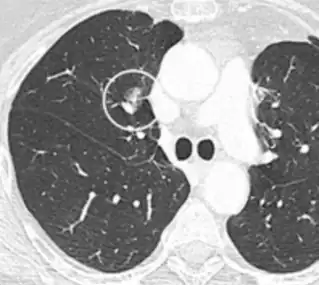

A "notch sign".[9]

A triangular perifissural node can be diagnosed as a benign lymph node.[9]